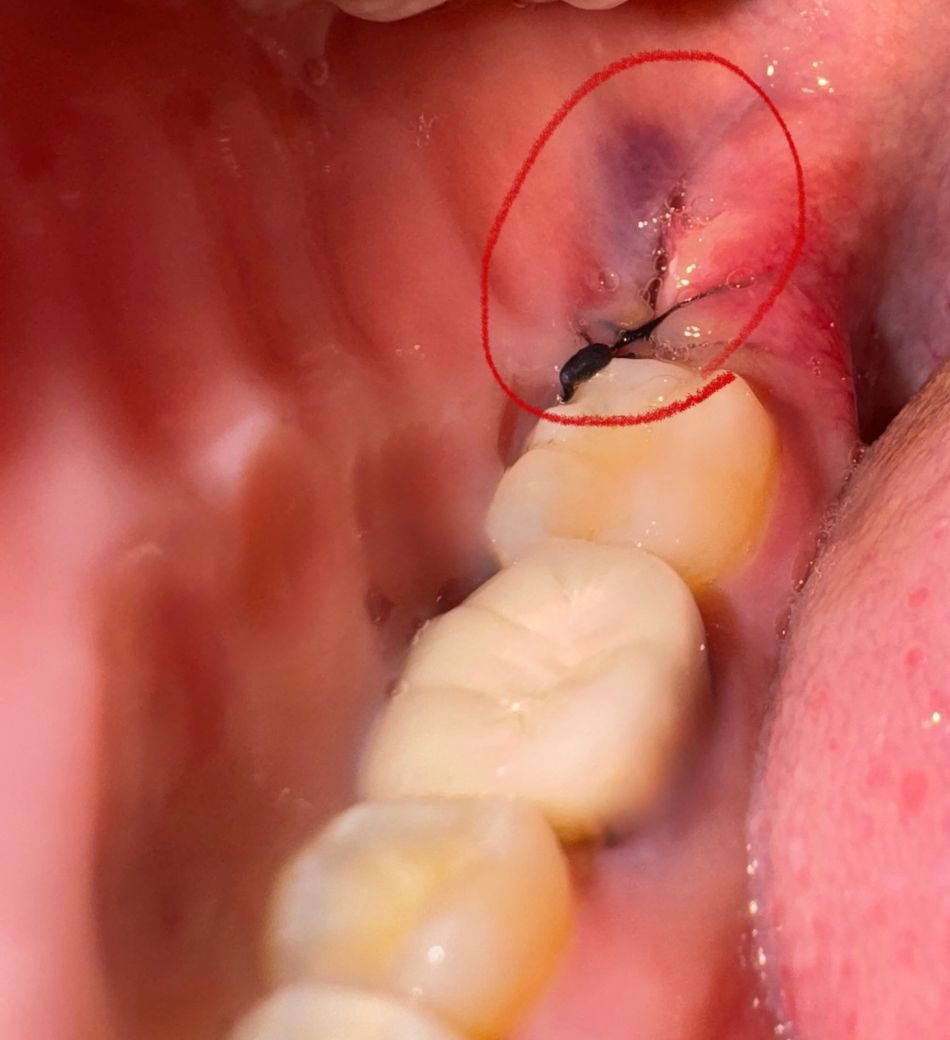

사랑니 발치한지 3일차인데 실밥이 풀렸어요(사진 약혐)

월요일에 발치해서 3일차입니다. 입 벌리다가 실밥이 툭툭 끊어지는 느낌이 들어서 보니까 봉합부분이 벌어진 거 같아서요... 옆에 멍도, 멍 근처에 노란빛을 띄는 것도 염증이 아닐까 걱정되는데 현재 휠체어 사용으로 당장 병원 내원이 힘들어서 질문 올려요ㅠ 재봉합 필요없을까요? 노란색은 염증인지... 통증은 그닥 없어요!

아시는 분 답변 부탁드려요ㅠㅠ 다음 내원은 월요일에 가기로 했어요

실밥이 풀린건 아닌거 같습니다. 잇몸의 붓기가 빠지면서 약간 느슨해 진거 같고 염증이 잇거나 그렇진 않습니다.

붓기가 빠지면서 느슨해진 것으로 보이며 회복에는 별다른 문제가 없으니 그대로 지내셔도 됩니다.

피 잘 멈췄으면 이 상태에서 다시 봉합을 해줄 필요는 없습니다. 사진상으로 치유에 문제가 있는 상황은 아닌 것 같습니다.